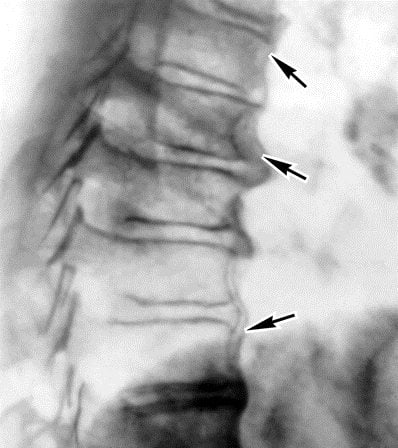

Характер клинического проявления зависит от состояния позвоночного столба. В результате компенсаторных нарушений физиологической осанки серьезно изменяется его конфигурация, что повышает интенсивность болезненных ощущений. Например, для длительно протекающего пояснично-крестцового остеохондроза характерен постоянный спазм скелетной мускулатуры в области нижних грудных позвонков, провоцирующий частичную деформацию позвоночника. Постепенно осанка человека изменяется из-за формирующейся холки на границе шейного и грудного отделов. Далее разрушаются межпозвонковые диски, расположенные выше этого образования. Пояснично-крестцовый и шейный остеохондроз оказываются патологически взаимосвязаны. Типичные деструктивные изменения хорошо визуализируются на рентгенографических изображениях. Этого достаточно для выставления диагноза «распространенный остеохондроз поясничного и шейного отдела позвоночника».

Если при рентгенографии обнаружены необратимые дегенеративные изменения в дисках на всех уровнях, необходима дифференциальная диагностика саркоидоза, болезни Бехтерева, амиотрофического бокового склероза. После их исключения выставляется диагноз «генерализованный остеохондроз».